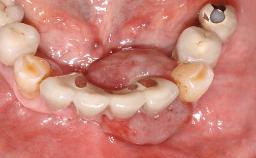

Surgical treatment of a 32-year old, healthy and non-smoking female who required removal and replacement of a lateral maxillary incisor due to internal root resorption. The inflammatory process caused a reduction of the crestal bone level on the distal side of the tooth necessitating an augmentation procedure to meet the patient's high esthetic demands. Due to the high smile line, the thin soft-tissue biotype and triangular-shaped teeth several esthetic risk factors are present.

After flapless tooth removal and a healing period of 6 weeks a diameter-reduced two-piece implant is placed. The bone defect on the facial aspect is corrected with a contour augmentation using autologous bone chips covered with DBBM particles and a collagen membrane according to the Guided Bone Regeneration (GBR) approach.

Case Type Single-Tooth Space

Jaw Maxilla

Area Anterior

# of Teeth 1

# of Implants 1

Type of Implants Reduced-Diameter|Two-Piece